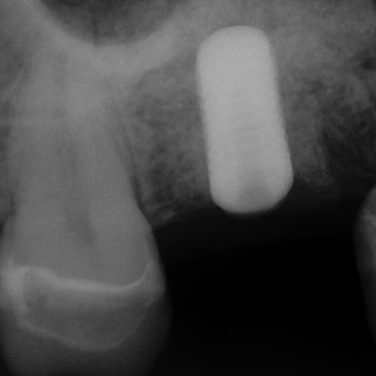

ULTRASONICS: Complications of Abutment Screw Retrieval Secondary to Prior Ultrasonic Attempts

There has been much written on the use of ultrasonics in retrieving fractured screw fragments, which I didn’t think a lot about until May of 2023, as it has not been a part of my fractured screw retrieval algorithm.